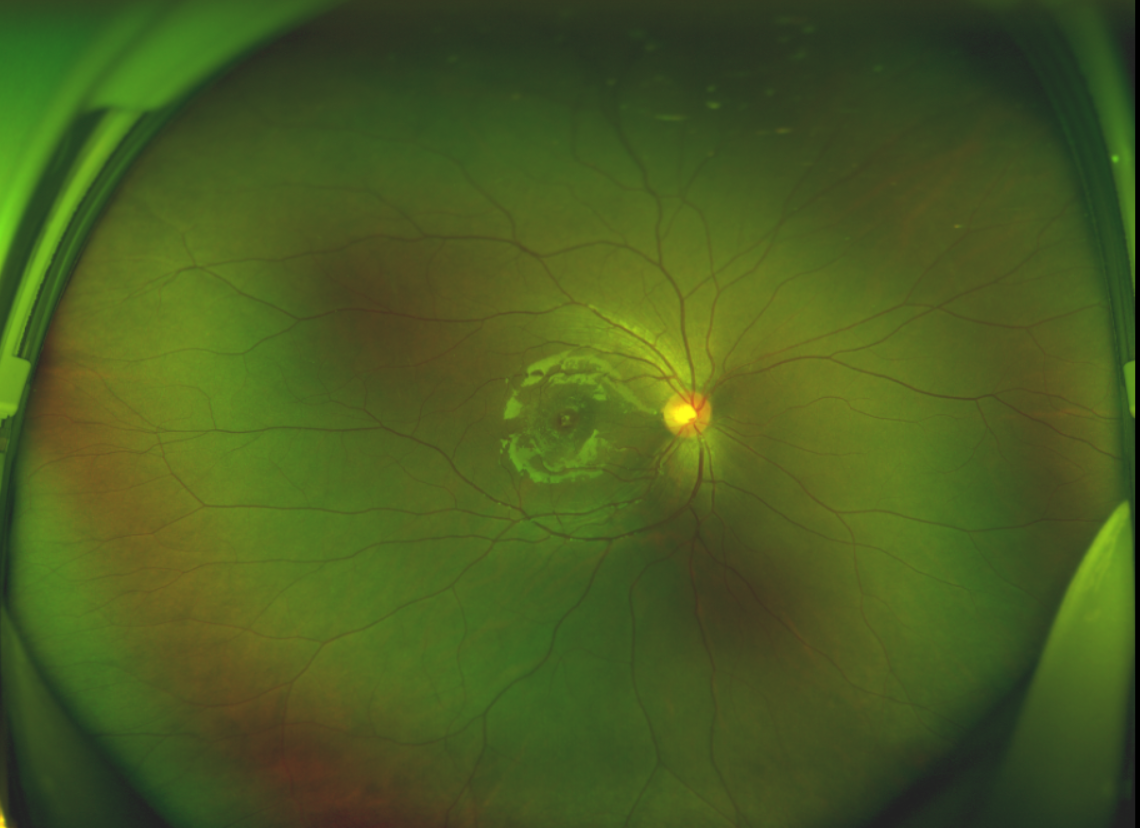

半年前的一次意外,誠(chéng)誠(chéng)(化名)右眼不慎受傷導(dǎo)致黃斑裂孔。從此,他的“視”界不再清晰,也不再有直線條……

黃斑位于視網(wǎng)膜正中心,是視覺(jué)最敏銳的區(qū)域,堪稱“眼底的心臟”,負(fù)責(zé)我們閱讀、駕駛、識(shí)別人臉等精細(xì)視覺(jué)。 當(dāng)黃斑區(qū)的神經(jīng)組織出現(xiàn)全層缺損,形成一個(gè)“孔洞”,即為黃斑裂孔,它會(huì)直接導(dǎo)致中心視力急劇下降、視物變形、視野中心出現(xiàn)暗區(qū)。

由于裂孔較小,當(dāng)?shù)蒯t(yī)院建議先觀察,看看裂孔是否能夠自愈??砂肽陼r(shí)間過(guò)去了,誠(chéng)誠(chéng)傷眼的裂孔不僅沒(méi)有愈合的跡象,反而越來(lái)越大,這讓家長(zhǎng)的心揪得更緊了。

經(jīng)過(guò)詳細(xì)的檢查和評(píng)估,王曉波主任決定采用“內(nèi)界膜翻轉(zhuǎn)覆蓋聯(lián)合粘彈劑固定術(shù)”為誠(chéng)誠(chéng)進(jìn)行治療。

除此之外,利用自體組織覆蓋為黃斑裂孔提供了理想的愈合環(huán)境,裂孔閉合速度顯著快于傳統(tǒng)方法。誠(chéng)誠(chéng)接受手術(shù)24小時(shí)后,檢查可見(jiàn)內(nèi)界膜瓣位置良好;術(shù)后1個(gè)月,黃斑裂孔已經(jīng)閉合,視力恢復(fù)到0.5;術(shù)后兩個(gè)月,視力進(jìn)一步提升到0.7。